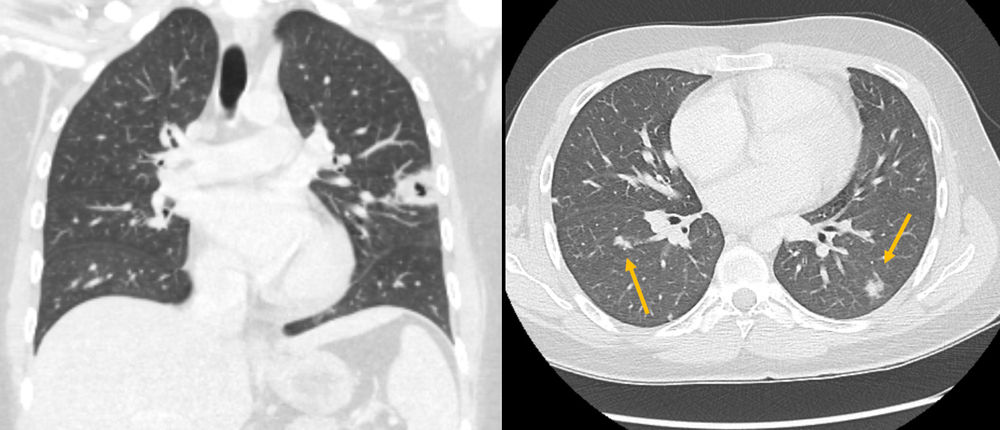

Sonographisch wird eine Thrombose der Vena jugularis interna (VJI) links festgestellt. Im Röntgenbild zeigt sich eine Kaverne im linken Oberlappen, in der Computertomographie weitere Rundherde in allen Lungenlappen.